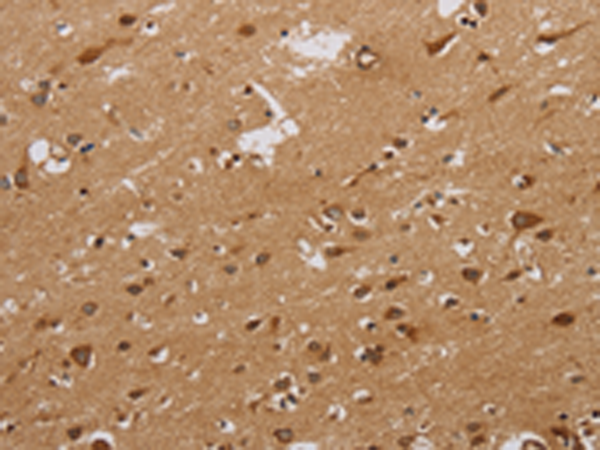

分类: 科研抗体货号: P10634别名: G-21; 5HT1a; PFMCD; 5-HT1A; 5-HT-1A; ADRBRL1; ADRB2RL1应用: WB,IHC反应种属: Human, Mouse, Rat